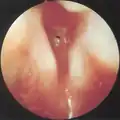

CT scans and MRI (magnetic resonance imaging) can help in diagnosis. X-rays can determine the location and size of the narrowed airway portion. Optical coherence tomography (OCT) can help observe the progression of the injury. Esophageal pH monitoring can help detect any acid reflux, which can worsen the condition. A laryngoscopy or an endoscope can be inserted and used to see the vocal cords, airway, and esophagus/trachea. Spirometry is a useful way to measure respiratory function. People affected by subglottic stenosis have a FEV1 of over 10.[2]

Subglottic stenosis is graded according to the Cotton-Myer classification system from one to four based on the severity of the blockage. Grade 1 is up to 50% obstruction, Grade 2 is 50-70% obstruction, Grade 3 is 70-99% obstruction, and Grade 4 is with no visible lumen.[5]